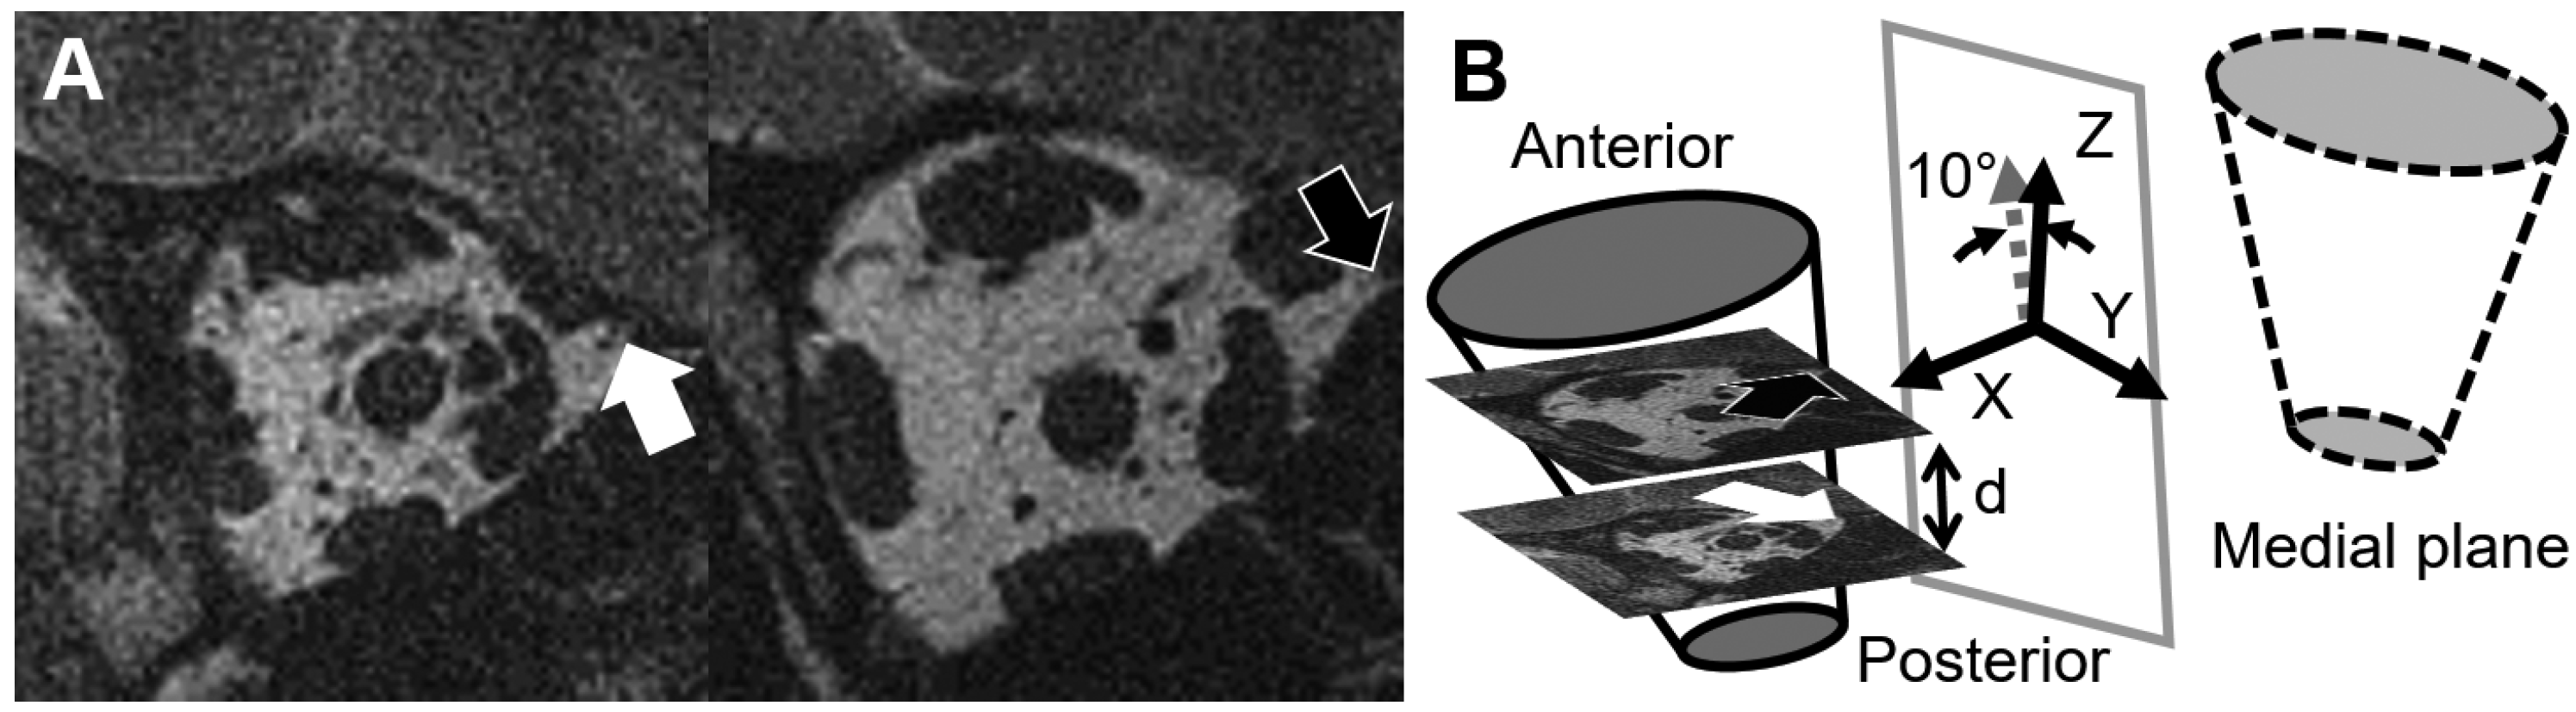

2.6. Local Coordinate Systems for the ON and the Reconstruction of the ON

2.7. Displacements and Strains

2.3. Curve Parametrization

2.4. Local Coordinate System for the Globe and Globe Translation